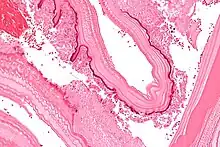

Micrograph showing the characteristic laminated cyst wall.H&E stain.

Laminated layer of a cyst found in a corpse in a grave from the late Roman period in France, interpreted[50] as a probable hydatidosis cyst